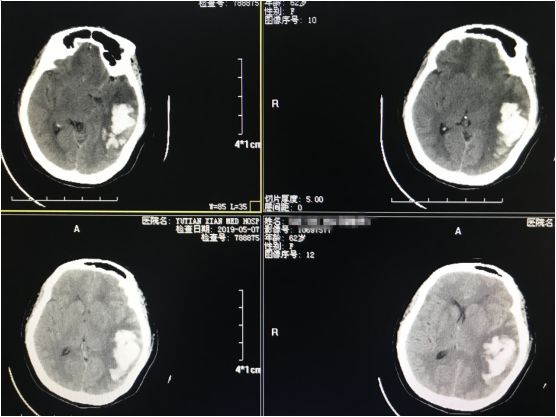

病例二:患者,女性,62岁,主因“突发右侧肢体活动不利、失语约2小时”入院,入院后查头颅CT如下:

▉入院时颅脑CT如图所示